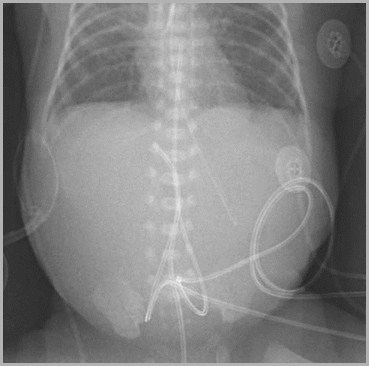

Two UACs, one in internal iliac, other in aorta

Auckland

Two UACs, one at T7, the other at L3UVC in portal vein

T7

L3